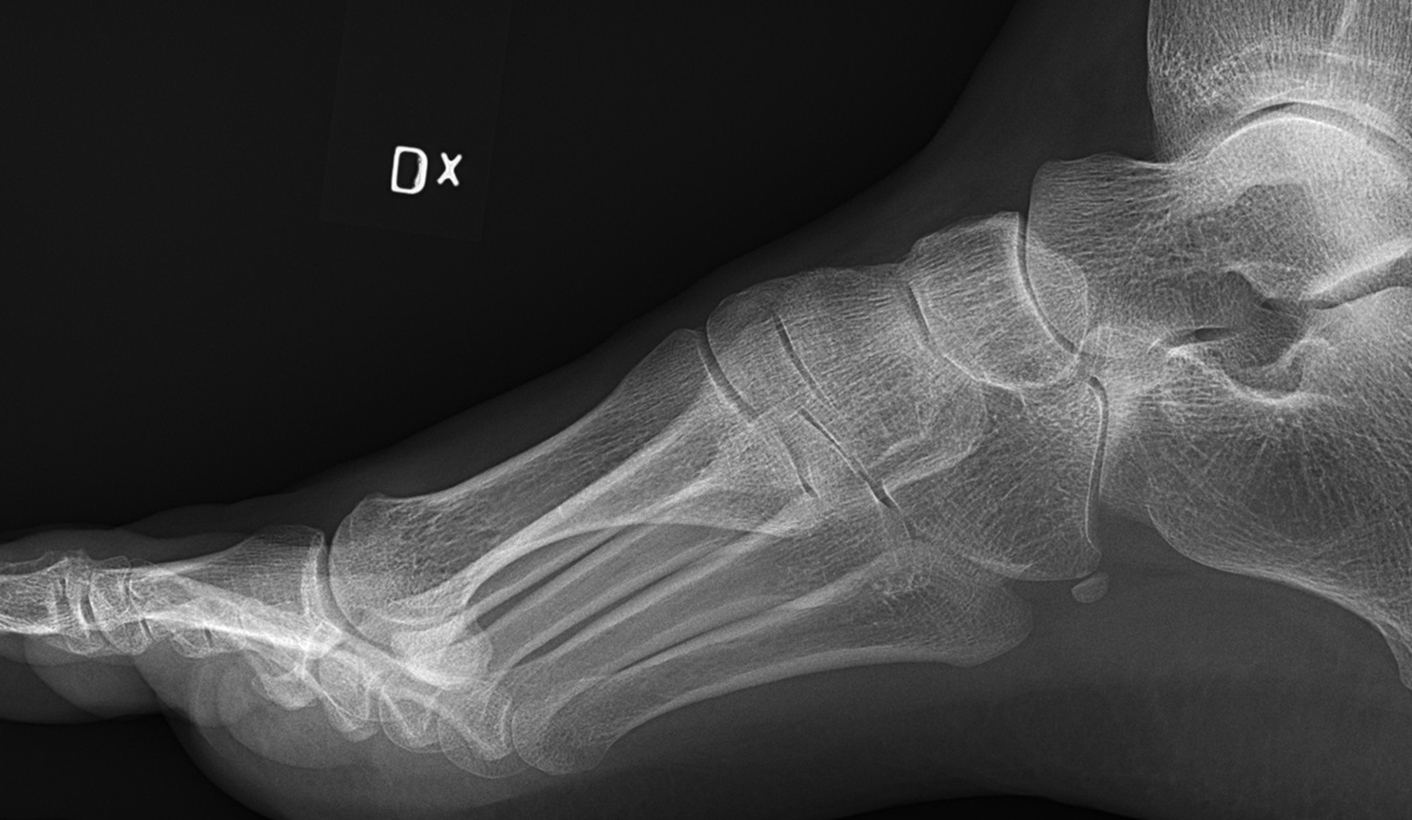

Whistle-blowers say patients with broken legs, arms and other serious orthopaedic conditions are being sent home in the Free State because the buckling health system is simply unable to cope with the numbers. Healthworkers are told there is no money to bring in outside help to reduce the waiting lists.

There are adults with trauma fractures, children with broken limbs and elderly patients with fractured hips. They are lying in overflowing hospital beds and in the passageways on trolleys and on the floor.

The domino effect of long waiting lists for orthopaedics is more complications, septic bed sores for the elderly, children left disabled and adults losing their jobs.